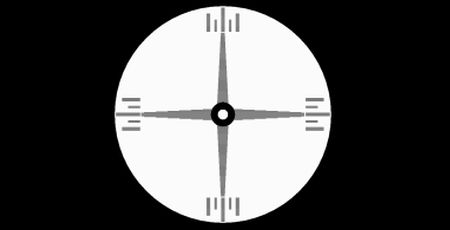

Wir haben die Lösung für Sie

Als Spezialisten für gutes Sehen widmen wir unsere besondere Aufmerksamkeit dem Auffinden nicht-idealer Bildlagen. Hierbei gelangt mit der MKH-Methodik eine sensible optometrische Untersuchungsmethode zur Anwendung, mit deren Hilfe auch seitliche Bildlagefehler sicher identifiziert und korrigiert werden können. Die augenoptische Korrektion erfolgt in der Regel mit präzisen prismatischen Brillengläsern, die das Bild in der Mitte der Netzhautgrube abbilden, den Augenmuskeln damit das ständige "Anziehen" abnehmen und so ein entspanntes Sehen ermöglichen. Sie werden sehen und erleben.